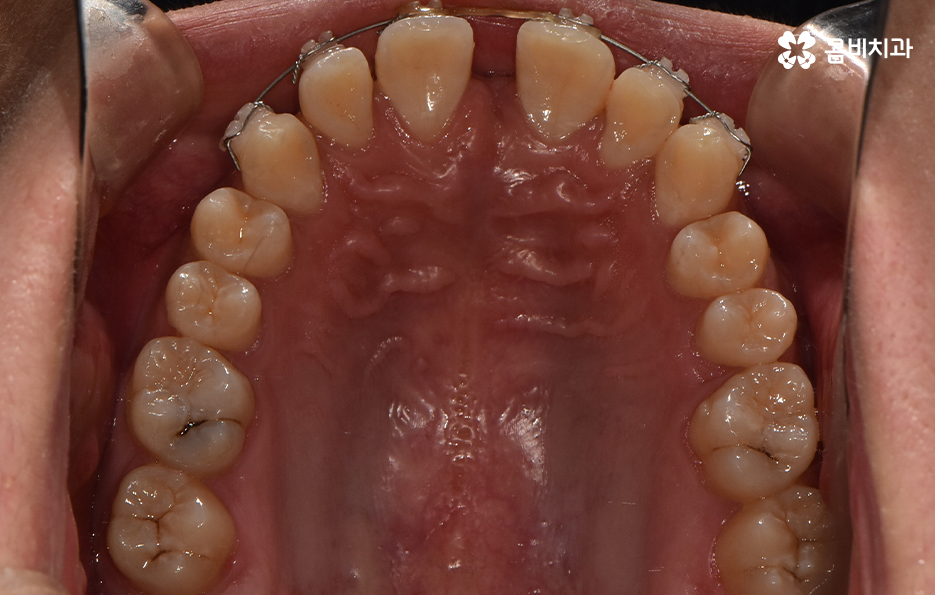

과잉치 중에서는 어떤 치아가 과잉치인지 구분이 어려울 정도로 일반적인 정상 치아의 크기와 비슷한 크기와 형태를 띄는 경우도 있는 반면에 위 사진의 케이스는 첫번째 앞니와 앞니 사이에 유독 작은 왜소치가 있는 형태이기 때문에 치아의 기능적인 문제 보다는 심미적인 개선을 필요했던 케이스로 볼 수 있어요

그나마 다행인 점은 앞니만교정을 하더라도 치아의 교합이나 골격적인 부분, 얼굴형 등에 있어서 큰 지장은 없던 경우였는데요. 물론 아랫니가 다소 벌어져 있기 때문에 전체교정을 하면 더 좋은 결과를 얻을 수 있었겠지만 환자분의 니즈에 있어서 앞니만교정을 빠르게 원했던 사례이기 때문에 앞니 부분의 과잉치 발치 후 앞니만교정을 부분적으로 진행했어요

과잉치로 인해 말그대로 치아의 정상 범위 이상으로 치아가 배열되기 때문에 다른 치아의 배열에도 악영향을 주는 경우가 많지만 위 환자분의 케이스의 경우에는 치열 자체는 전체적으로 가지런한 편이라는 점과 특히 턱뼈가 넓은 편이라는 점에서 전체교정을 하지 않았어도 환자분이 원하는 치료의 목표는 달성할 수 있었어요

치아교정 기간은 각 환자분들에 따라 천차만별이기 때문에 정확하게는 각 환자분들의 상태를 직접 확인해봐야 하며 누구나 앞니만 부분적으로 교정이 가능한 것은 아니기 때문에 정밀검진이 우선적으로 필요하며 위 환자분의 경우에는 과잉치를 발치하고 교정기 장착 후에 약 6개월 정도가 지나서 교정기를 떼어낼 수 있었어요